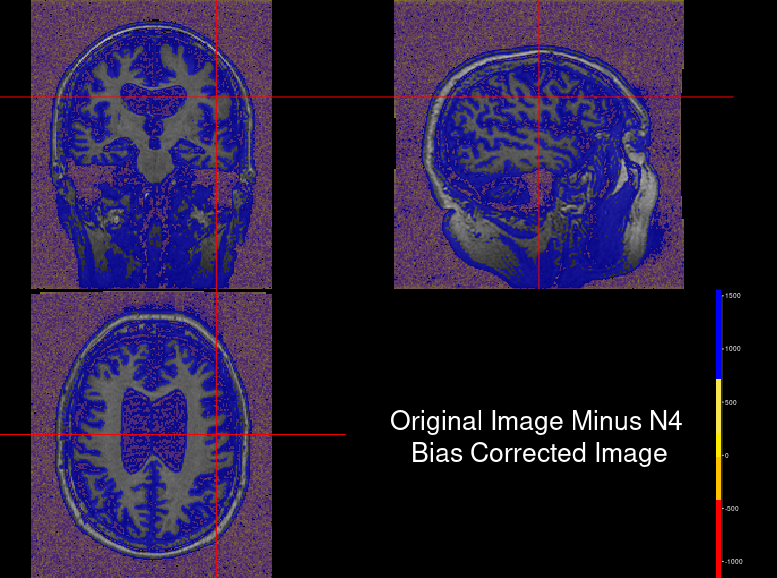

The N4 algorithm then uses a robust B-spline approximation algorithm of the bias field and iterates until a convergence criterion is met where the modified bias field is approximately similar to the last performed iteration. After the updated transformation, the image is outputted back into the original file using inverse log transform. To visualise the effects of bias field correction Fig 3 shows a sample patient scan in all three planes by applying N4 bias correction using ANTsR library in R.

Figure 3: Inhomogeneity correction: (a) Source Scan (b) Bias Field Corrected Scan (c) Bias field corrected scan subtracted from source scan

Even though visually, there might not be a stark difference in the corrected scan, white and grey matter intensities are uniform in distribution compared to the source image. Fig 3(c) helps to visualize the difference where the blue gradient represents higher differences. It becomes imperative how there was a slowly varying field existing in the source image, which was removed in the corrected version.